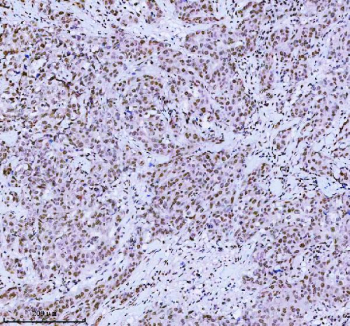

Immunohistochemical staining of MED4 using anti-MED4 antibody. MED4 was detected in a paraffin-embedded section of human spleen tissue. Heat mediated antigen retrieval was performed in EDTA buffer (pH 8.0, epitope retrieval solution). The tissue section was blocked with 10% goat serum. The tissue section was then incubated with 2 ug/ml rabbit anti-MED4 antibody overnight at 4oC. Peroxidase Conjugated Goat Anti-rabbit IgG was used as secondary antibody and incubated for 30 minutes at 37oC. The tissue section was developed using an HRP secondary and DAB substrate.